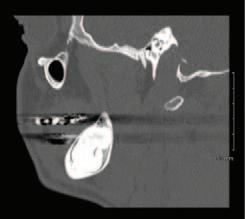

2. Wright, J.T., Crall, J.J., Fontana, M., Gillette, E.J., Nový, B.B., Dhar, V., et al Evidencebased clinical practice guideline for the use of pit-and-fissure sealants: a report of the American Dental Association and the American Academy of Pediatric Dentistry. J Am Dent Assoc 2016; 147 (8): 672-682.e12.

3. Lygidakis, N.A., Garot, E., Somani, C., Taylor, G.D., Rouas, P., Wong, F.S.L. Best clinical practice guidance for clinicians dealing with children presenting with molar-incisorhypomineralisation (MIH): an updated European Academy of Paediatric Dentistry policy document. Eur Arch Paediatr Dent 2022; 23 (1): 3-21.

4. Frencken, J.E. The state-of-the-art of ART sealants. Dent Update 2014; 41 (2): 119-120, 122-124.

CLINICAL TIPS

FIGURE 2: Effective cotton wool roll isolation. FIGURE 3: Conditioning of the pits and fissures. FIGURE 4a: Application of a GI sealant (GC Fuji IX). FIGURE 4b: Manipulation into the pits and fissures using the ‘finger press’ technique.

30 Journal of the Irish Dental Association | February/March 2023: Vol 69 (1)

FIGURE 5: GI fissure sealant.

A sagittal split osteotomy approach for removal of a large cementoblastoma at the mandibular angle

Précis

This case report demonstrates the effectiveness of sagittal split osteotomy in the removal of a mandibular cementoblastoma.

Abstract

Benign lesions at the angle of the mandible are frequently removed by a conventional intra-oral approach to gain access and achieve complete visualisation. This method is quick and effective when dealing with small, benign lesions that are superficially located at the angle of the mandible. The removal of large and deeply located lesions with a conventional intra-oral approach, however, brings about a unique set of challenges, particularly when the third molar is displaced towards the inferior border of the mandible, including: lack of complete visualisation of the lesion; difficulty in identification and protection of the inferior alveolar nerve; and, the necessity of removing a considerable amount of osseous structure, thus increasing the risk of a mandibular fracture. Alternative techniques for such lesions include an extra-oral approach, but this could potentially create a cosmetic defect from cutaneous scarring and can result in facial nerve injury.

This case report describes the use of a unilateral sagittal split osteotomy (SSO) in the removal of a mandibular cementoblastoma. This is a safe and effective technique allowing optimal access to the tumour with complete visualisation, identification and protection of the inferior alveolar nerve, and with minimal bone removal, while maintaining mandibular integrity, strength and facial aesthetics.

Introduction

A cementoblastoma, also referred to as a true cementoma, is a rare, benign odontogenic tumour arising from ectomesenchymal cells.1 They have also been referred to in the literature as: sclerosing cementoma; peri-apical fibroosteoma; and, peri-apical fibrous dysplasia. Disorganised proliferation of cementoblasts results in subsequent deposition of cement-like tissue around the roots of teeth. Cementoblastomas account for between 0.69% and 8% of all odontogenic tumours and tend to occur between the second and third decades of life, with a median age of 20 years and an age range of eight to 44 years. Some studies show no gender preference,2 while others show a higher rate of occurrence in males.3 Cementoblastomas tend to occur more frequently in the posterior mandible, involving the roots of premolar and

molar teeth. They are asymptomatic lesions, which demonstrate a slow and expansile growth, and are usually discovered as an incidental radiographic finding.4 However, cortical bone expansion can result in facial asymmetry and symptomatic painful lesions when facial nerves become involved.5 Because cementoblastomas have unlimited growth potential, treatment includes tumour resection with the extraction of the associated tooth. If the tumour is small at the time of diagnosis, treatment may consist of surgical removal with endodontic therapy and retention of the involved tooth. The traditional surgical approach for excision of a cementoblastoma at the mandibular angle is removal of bone to gain access to the tumour. However, the surgical risk increases with removal of larger lesions via traditional techniques, which will involve the removal of larger amounts of bone,

PEER-REVIEWED

Journal of the Irish Dental Association February/March 2023; 69 (1): 31-35

BA APsych BDS NUI MFD RCSI MB BCh BAO Surgical SHO

BDS

FFDRCSI

Registrar in Oral and Maxillofacial Surgery South Infirmary Victoria University Hospital Cork

FDS

in Oral and Maxillofacial Surgery South Infirmary Victoria University Hospital Cork Corresponding author: Dr Mar Cotter. E: mcottdentist@gmail.com Journal of the Irish Dental Association | February/March 2023: Vol 69 (1) 31

Dr Mar Cotter

Mr Zeeshan G. Khattak

MSc OMFS MFDS RCPS